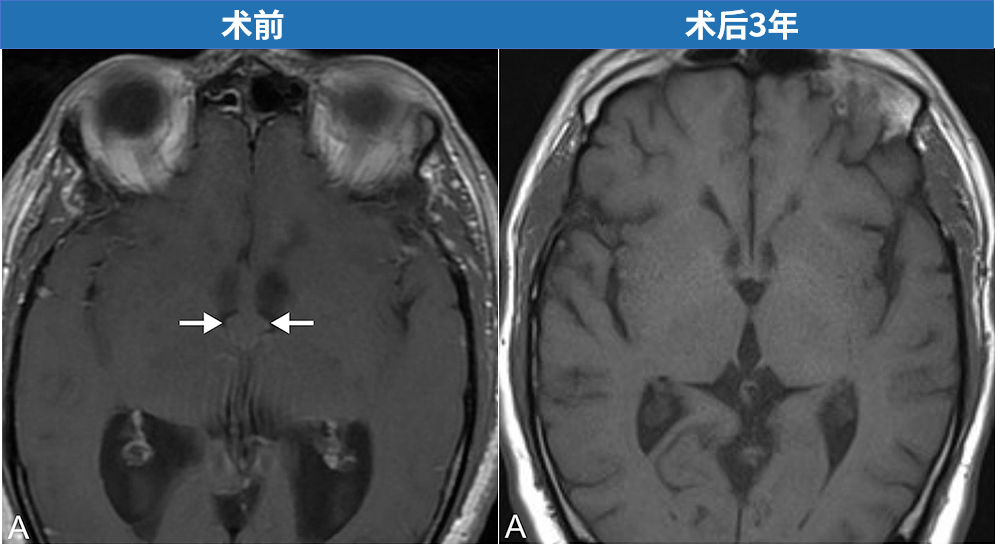

一位55岁男性患者因进行性步态障碍与记忆力持续减退前来就诊,影像学检查显示存在脑积水。头颅磁共振成像(MRI)进一步明确诊断为第三脑室胶样囊肿伴梗阻性脑积水。由施罗德教授主刀,为该患者实施了神经内镜下第三脑室胶样囊肿切除术。术后三年随访结果显示囊肿已完全切除,未见复发迹象。

手术结束前,分别使用30度和45度诊断性内镜对脑室系统进行全面检查,确认无囊肿残留,并排除囊内实性成分堵塞中脑导水管的可能性。钻孔处以明胶海绵填塞,帽状腱膜严密缝合,皮肤以无创伤缝线连续缝合。术后三年复查MRI显示囊肿全切,无残留与复发,脑室系统形态恢复良好。